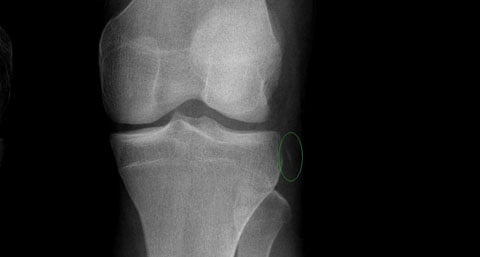

Et c’est à partir de ces observations, que Paul Segond laissera son nom à la fracture de Segond (Fig. 1). Cette fracture est une fracture par avulsion (i.e., par arrachement) et elle est systématiquement observée lors de la rotation interne de la jambe. Pour Segond, “les fibres nacrées et résistantes qui forment la partie antéro-externe du surtout fibreux articulaire et dont nous avons signalé plus haut le degré de tension extrême, lorsque la jambe est tordue en dedans, exercent une traction violente sur leur point d’insertion et l’arrachent. Ce n’est jamais le tubercule de Gerdy qui cède, mais la portion d’os située immédiatement en arrière. Peut-être faut-il en chercher la raison dans la moindre résistance du tissu osseux en ce point. Quelle que soit d’ailleurs l’explication, le fait est constant, et c’est là ce qu’il faut retenir“.